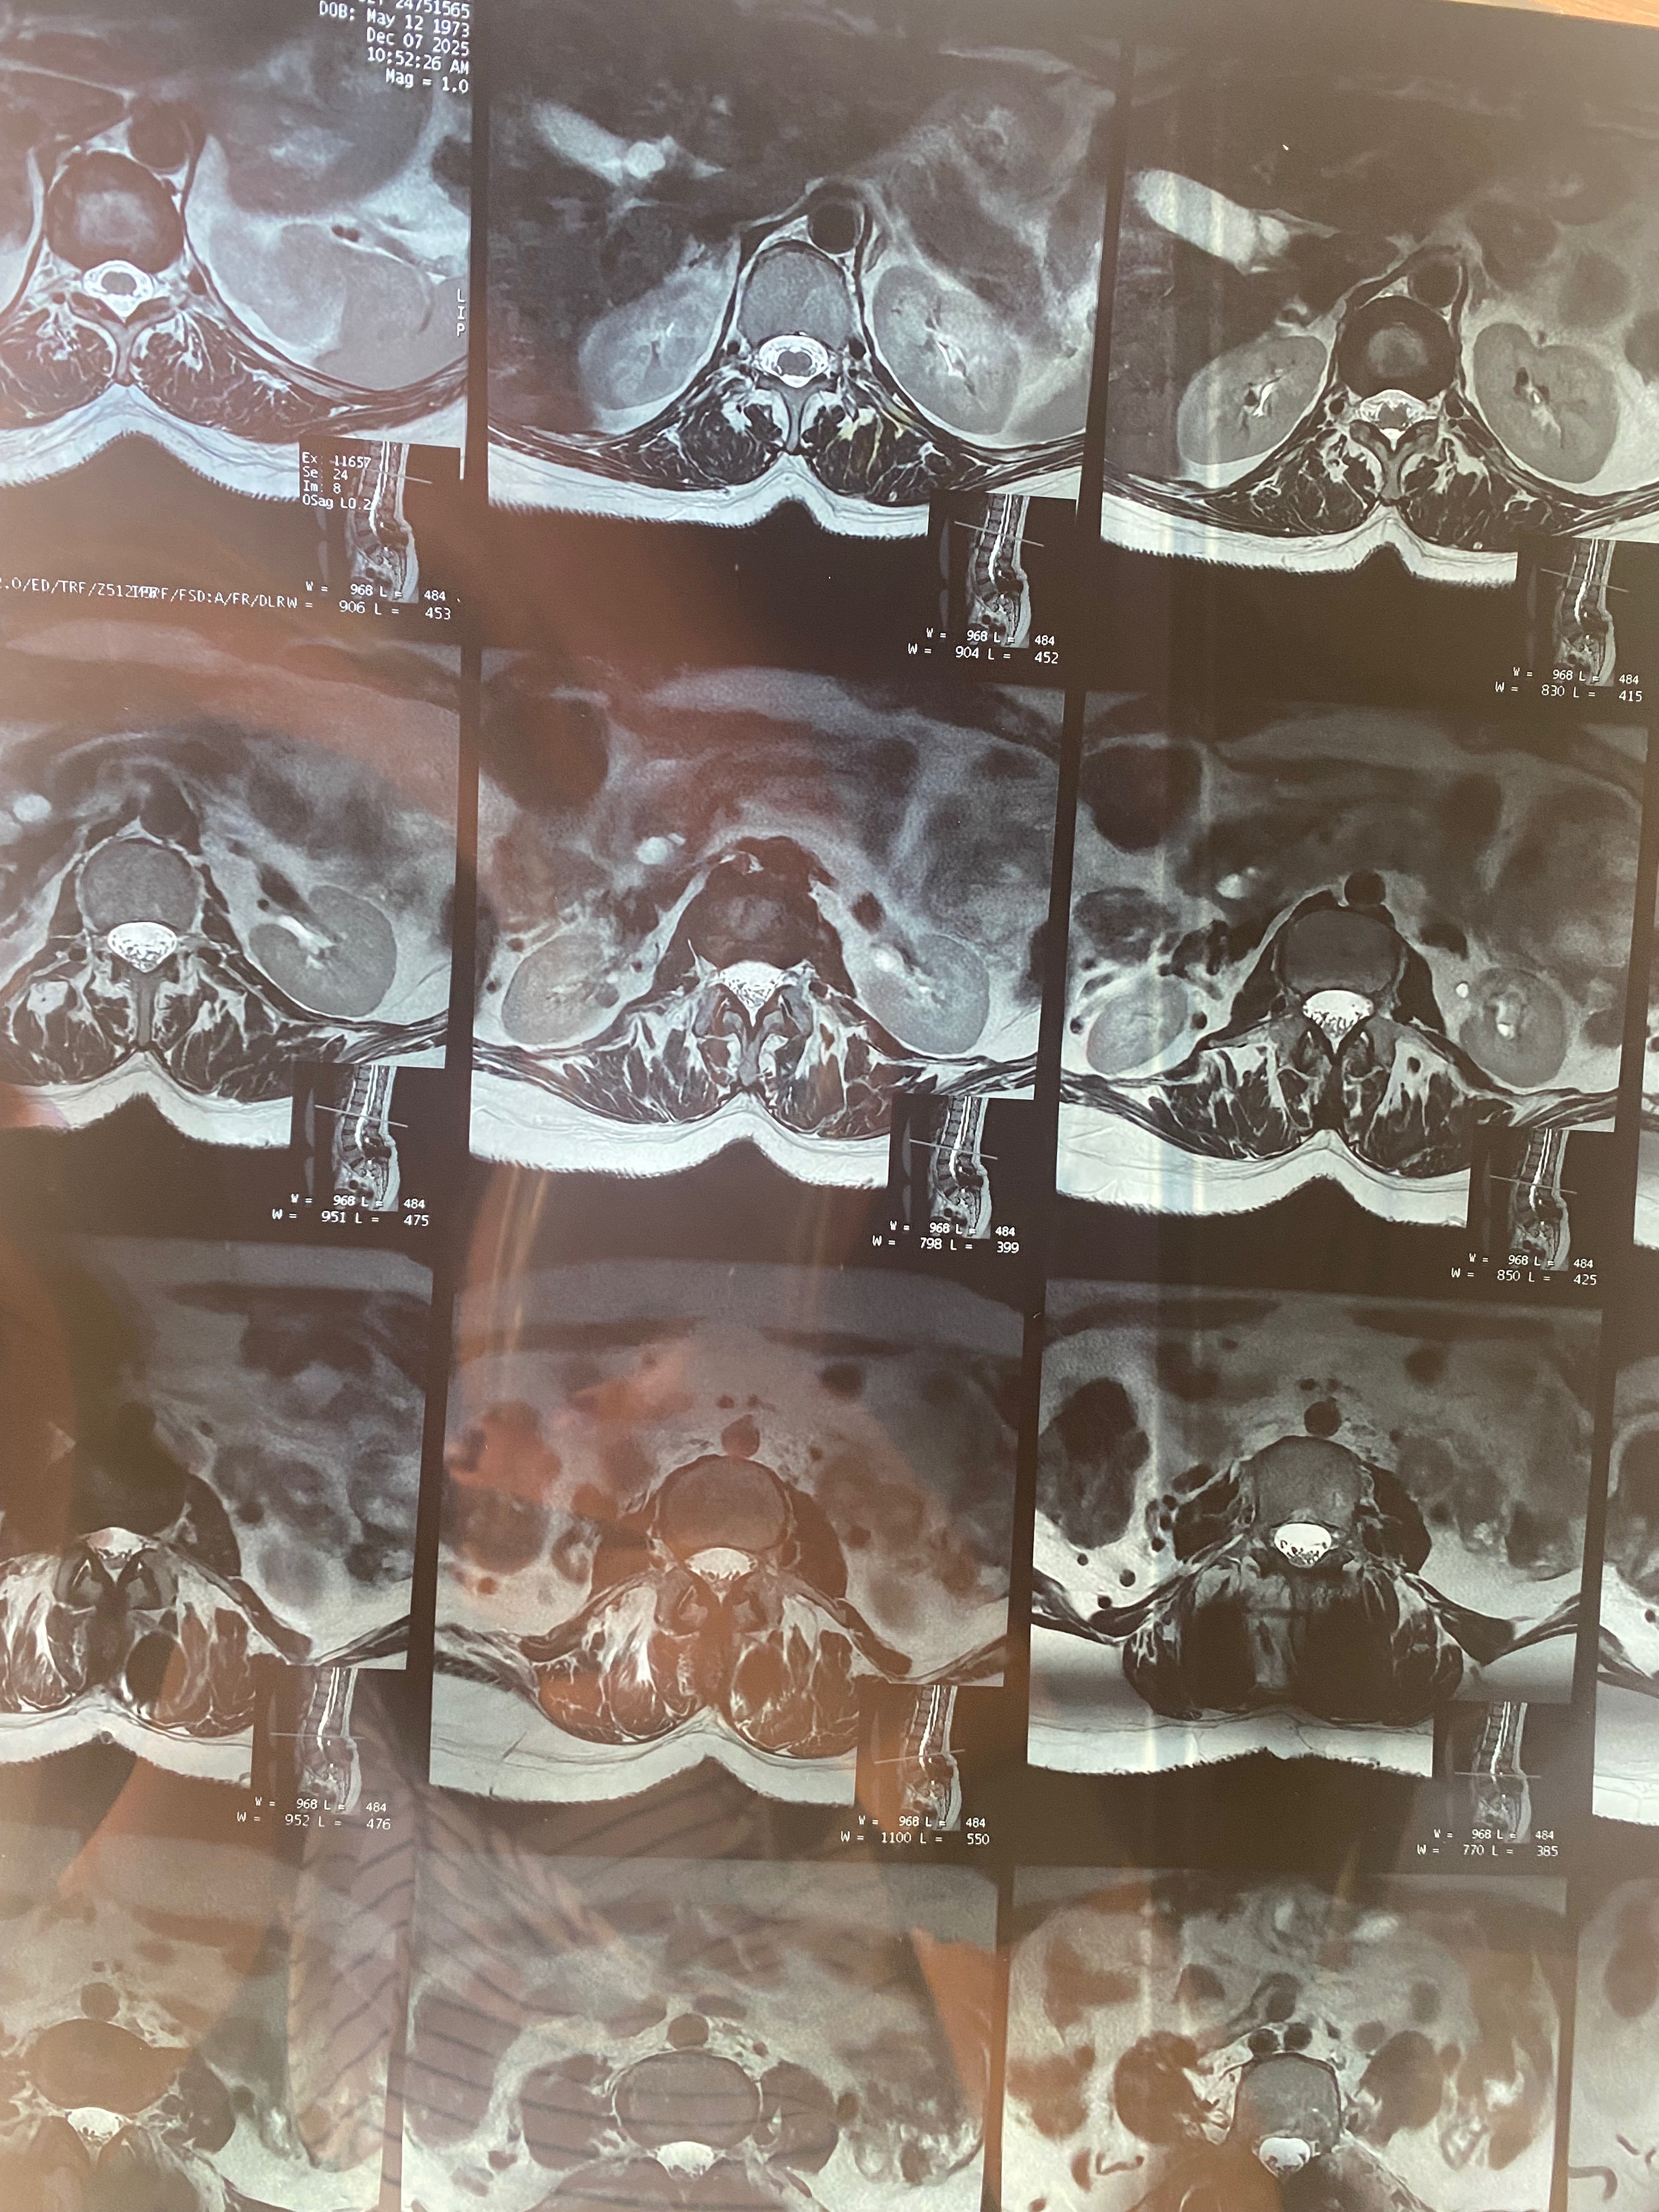

Hace 28 años, mi mamá fue operada de la columna y le colocaron prótesis de metal que, con el paso del tiempo, dejaron de ser funcionales. En los últimos meses, su condición ha empeorado: presenta dolor constante, adormecimiento en las piernas, mareos y una dificultad cada vez mayor para caminar, sentarse y descansar.